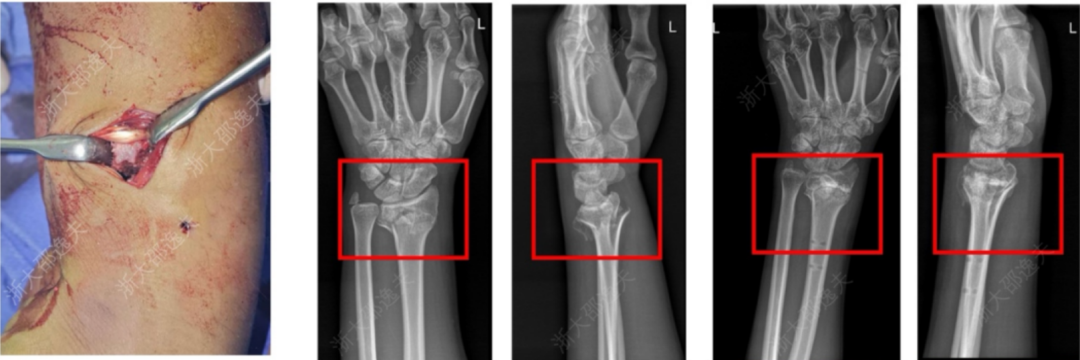

它在多家医院 150 余例受试病例中展现出了良好的安全性和有效性,各项指标达到预设标准。其中一位年轻工人因外伤致腕部粉碎性骨折,为避免传统的钢板内固定手术方案,医生通过一个 2-3 厘米的微创切口注入了“骨 02”,便黏合了碎骨。术后复查显示,患者骨折愈合良好,手腕功能得以恢复。

来源:见水印